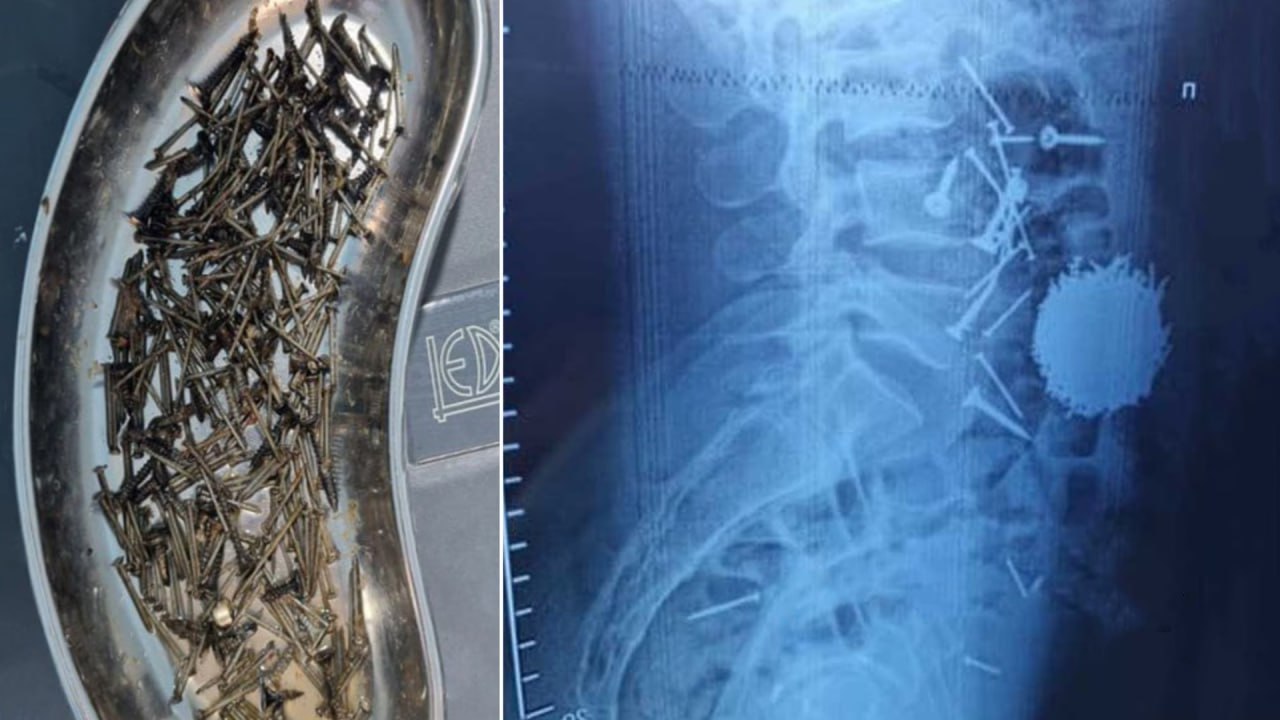

В Самарканде мужчине удалили из желудка более 200 граммов гвоздей и саморезов В Самаркандском филиале Республиканского научного центра экстренной медицинской помощи был госпитализирован 29 летний мужчина с сильными болями в области живота сообщает пресс служба учреждения English O zbek tilida Ўзбек тилида На русском iOS Android

В Самаркандском филиале Республиканского научного центра экстренной медицинской помощи 29 летний мужчина с болями в животе был прооперирован из за большого количества гвоздей и саморезов в желудке которые он проглотил в состоянии стресса

В Самарканде врачи извлекли из пациента почти 200 граммов гвоздей и саморезов Как сообщили медики мужчина проглотил металлические предметы на фоне сильного стресса Ему своевременно оказали медицинскую помощь Подписаться на канал Узбекистан Online

В Самарканде парень проглотил 200 граммов гвоздей и саморезов Врачи экстренно извлекли инородные предметы из тела пациента nova24 uz 317966 NOVA24 LIVE